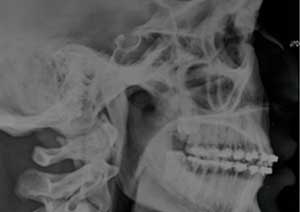

Le traitement de la supraclusion : Le traitement de la supraclusion repose avant tout sur un diagnostic précis, permettant de déterminer son origine dento-alvéolaire, squelettique ou mixte, ainsi que l’âge du patient.

Les objectifs principaux sont de réduire le recouvrement incisif, de rétablir une dimension verticale équilibrée et d’assurer une fonction occlusale stable.

Après

Radiographie après